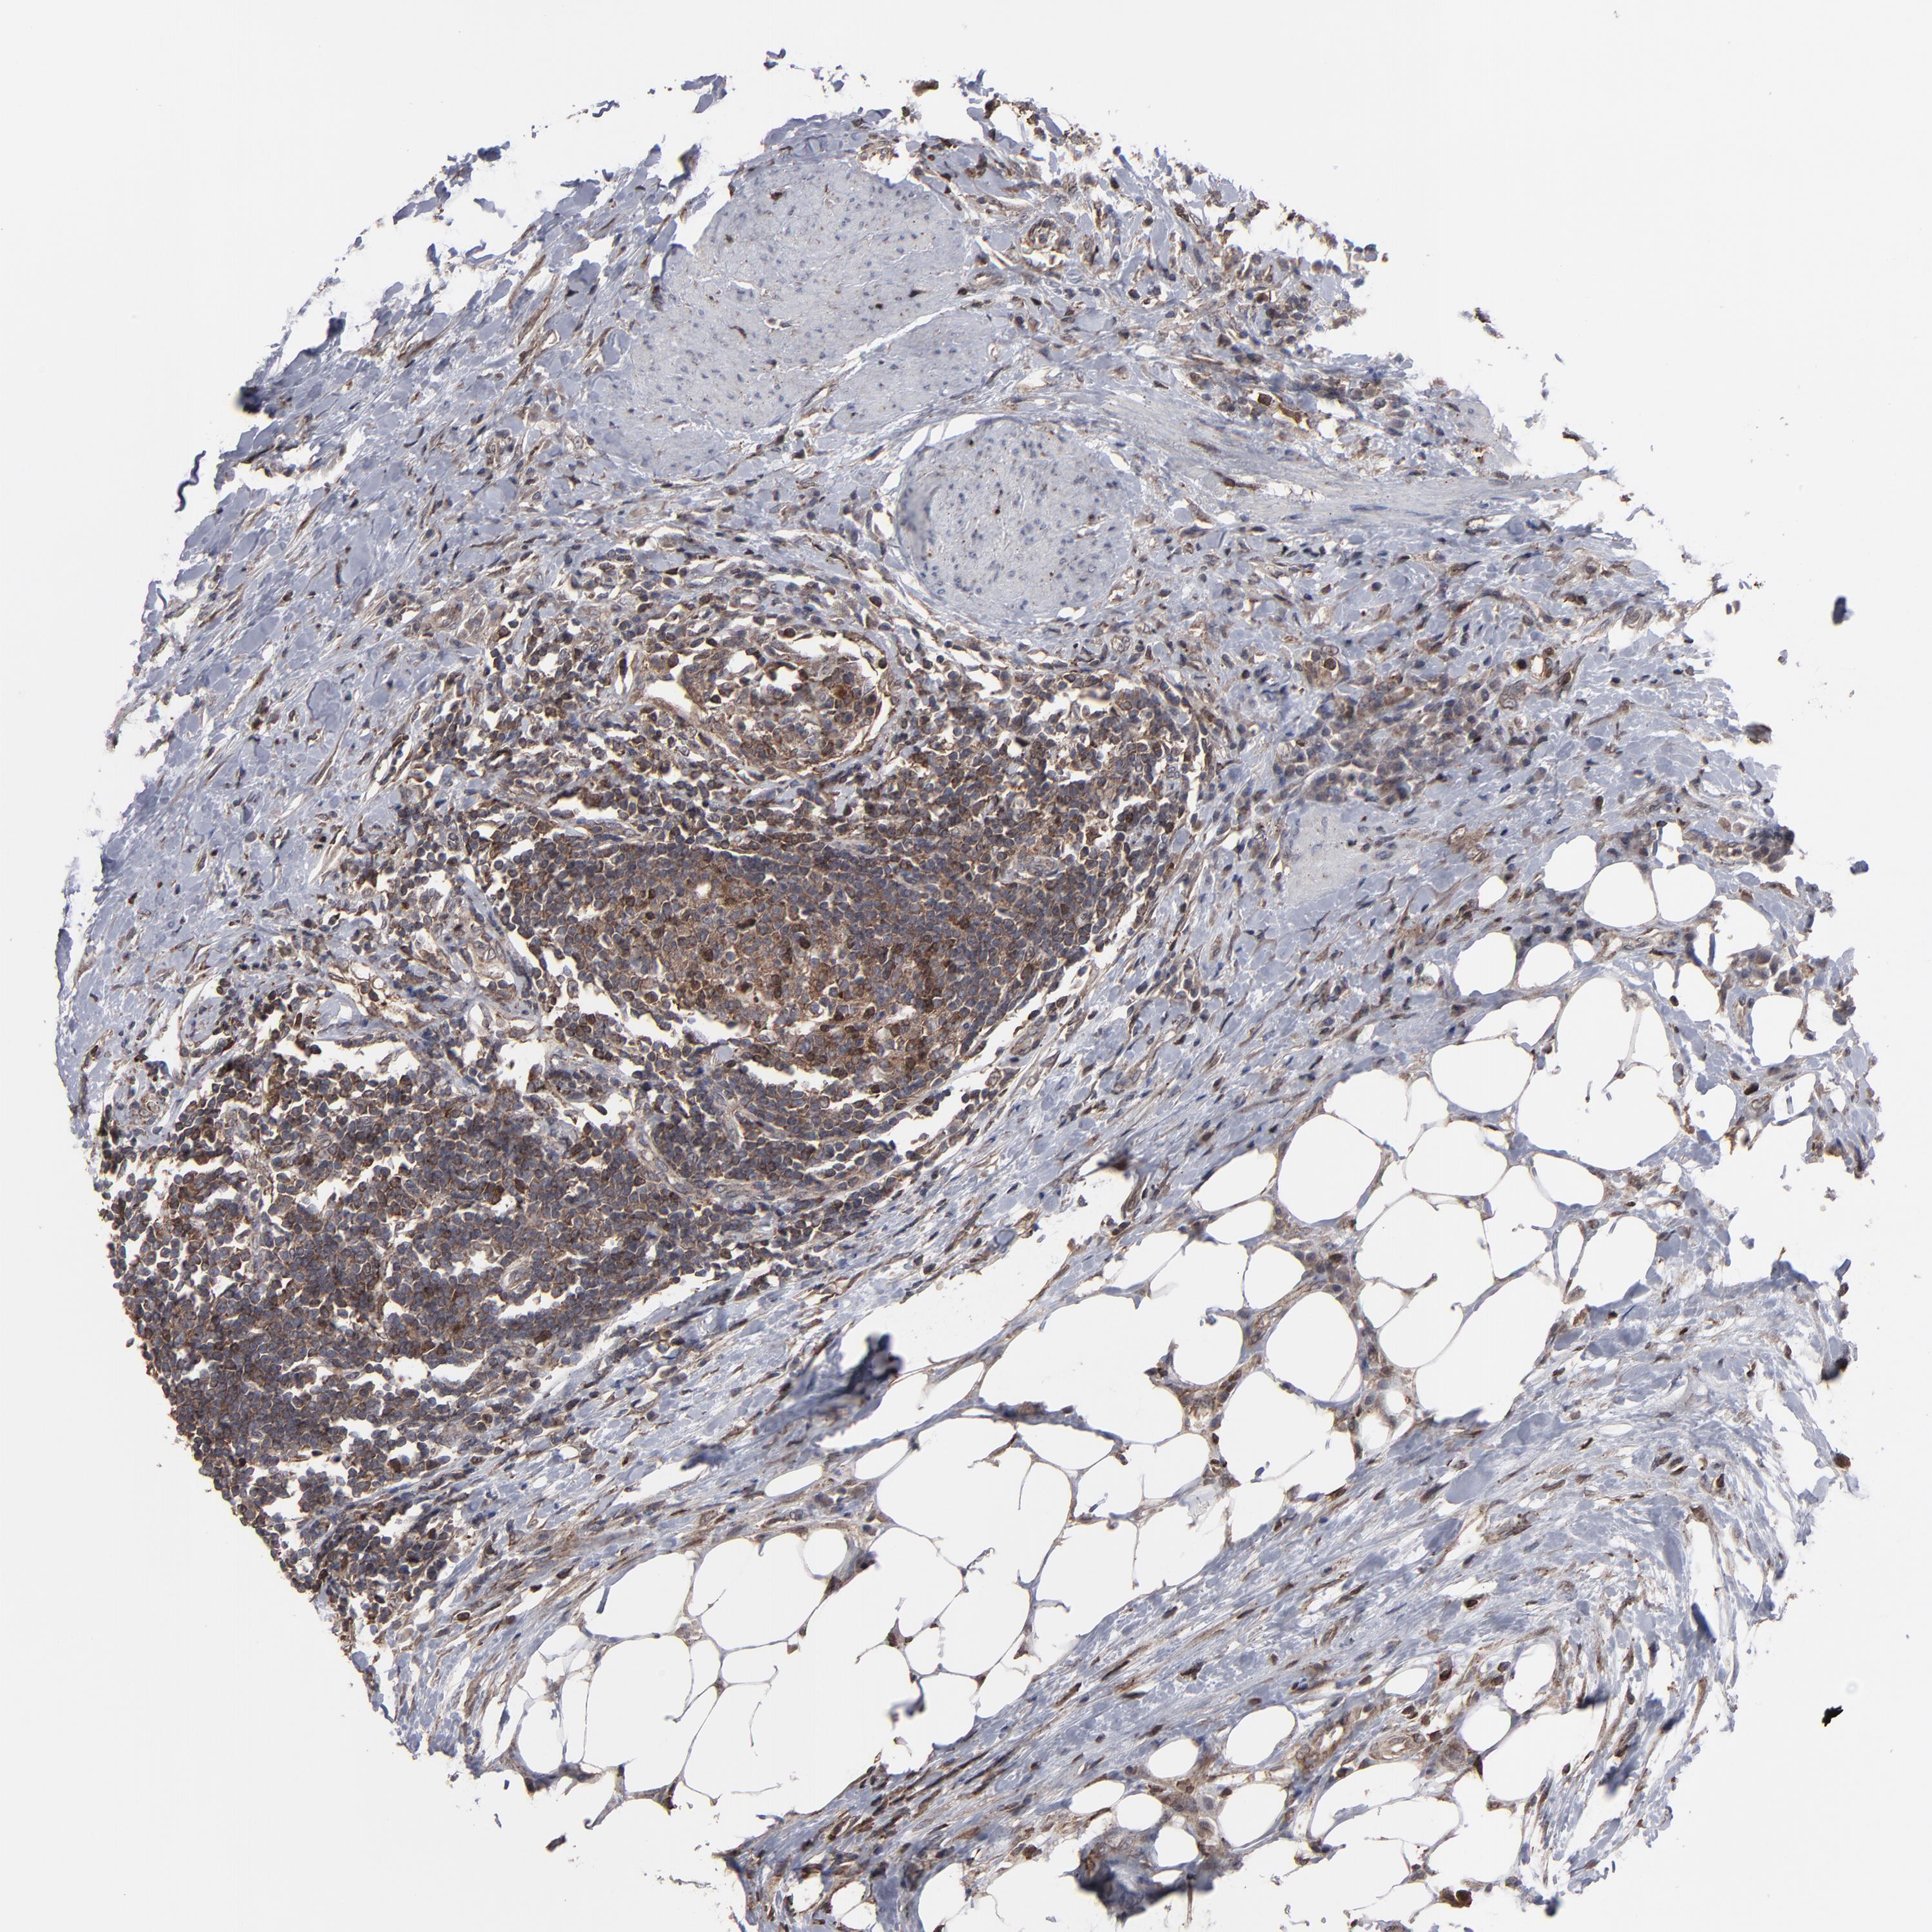

UROTHELIAL CANCER - Protein expressioni

A mouse-over function shows sample information and annotation data. Click on an image to view it in a full screen mode. Samples can be filtered based on level of antibody staining by selecting one or several of the following categories: high, medium, low and not detected. The assay and annotation is described here.

Antibody stainingi

Antibody staining in the annotated cell types in the current human tissue is reported as not detected, low, medium, or high, based on conventional immunohistochemistry profiling in selected tissues. This score is based on the combination of the staining intensity and fraction of stained cells.

Each image is clickable and will lead to virtual microscopy that enables deeper exploration of all samples and also displays staining intensity scores, fraction scores and subcellular localization as well as patient and tissue information for each sample.

Antibody HPA002109

Staining

High

Medium

Low

Not detected

Intensity

Strong

Moderate

Weak

Negative

Quantity

>75%

75%-25%

<25%

None

Location

Nuclear

Cytoplasmic/membranous

Cytoplasmic/membranous,nuclear

Urothelial carcinoma, High grade

Urothelial carcinoma, Low grade